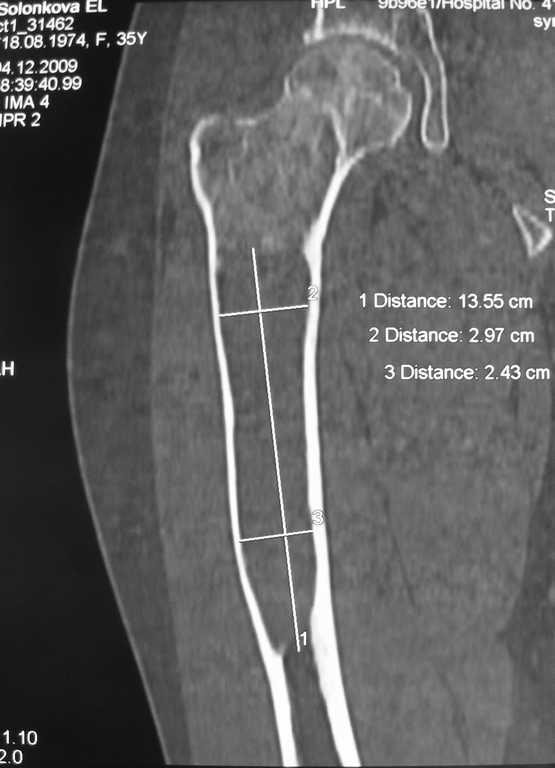

Уважаемые коллеги, доброго времени суток!

Большое спасибо всем, откликнувшимся на сообщение от 17 ноября

"Фиброзная дисплазия". В настоящее время пациентке выполнена

компьютерная томография и открытая биопсия правой бедренной кости с

последующим иммуно-гистохимическим исследованием.

Подтверждается диагноз фиброзной дисплазии без малигнизации.

Хотелось бы услышать мнение коллег относительно тактики дальнейшего

лечения пациентки, в первую очередь, варианты замещения дефекта в

случае резекции патологического очага с учётом обширности поражения.